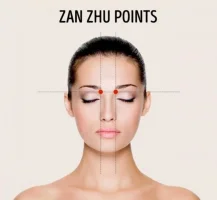

Hastalık, önceleri beyinde bir hasar kaynaklı olduğu düşünülmekteydi ancak son bulgular yüksek bir genetik ilişki olduğunu ortaya koymuştur. İncelemelerde beynin yüz tanıma ile ilgili temporal ve oksipital bölümlerinde bozukluk tespit edilmiştir.

Prosopagnostik bireylerden ikinci gruba dahil olanlarda ise fiziksel bir kitle ya da travma olduğu için bu bireyler hastalığın beyindeki hangi merkezlerden kaynaklandığı konusunda araştırmalara daha çok katkı verir. Bir felç, travma ya da beyin tümörü nedeniyle yüz tanıma yetisini kaybeden insanlarda sorun olan bölgelere bakılmış, beynin hangi bölgesinin yüz tanıma ile ilişkili olduğu bulunmaya çalışılmıştır. Bunun yanında fMRI(1) gibi görüntüleme tekniklerinin gelişmesi ile birlikte araştırmalar hızlanmış ve yüz tanıma yetisine sahip olmamızı sağlayan bölüm ortaya çıkarılmıştır. Bu bölüm fusiform yüz bölgesi olarak adlandırılmıştır.

Hastalık, önceleri beyinde bir hasar kaynaklı olduğu düşünülmekteydi ancak son bulgular yüksek bir genetik ilişki olduğunu ortaya koymuştur. İncelemelerde beynin yüz tanıma ile ilgili temporal ve oksipital bölümlerinde bozukluk tespit edilmiştir.

Prosopagnostik bireylerden ikinci gruba dahil olanlarda ise fiziksel bir kitle ya da travma olduğu için bu bireyler hastalığın beyindeki hangi merkezlerden kaynaklandığı konusunda araştırmalara daha çok katkı verir. Bir felç, travma ya da beyin tümörü nedeniyle yüz tanıma yetisini kaybeden insanlarda sorun olan bölgelere bakılmış, beynin hangi bölgesinin yüz tanıma ile ilişkili olduğu bulunmaya çalışılmıştır. Bunun yanında fMRI(1) gibi görüntüleme tekniklerinin gelişmesi ile birlikte araştırmalar hızlanmış ve yüz tanıma yetisine sahip olmamızı sağlayan bölüm ortaya çıkarılmıştır. Bu bölüm fusiform yüz bölgesi olarak adlandırılmıştır.